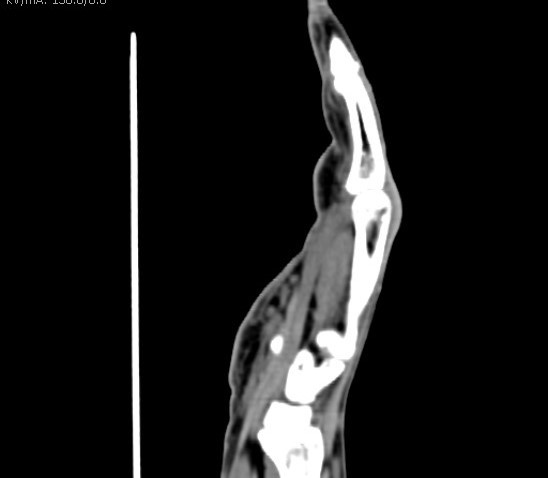

Medicom ExamesTomografia Computadorizada permite o médico iniciar um tratamento entendendo da real doença ou localização precisa da fratura de seu paciente, uma... Cotar Agora Saiba Mais

Medicom ExamesExames de tomografia torna possível ao médico começar um tratamento entendendo a real doença ou localização exata da fratura de seu paciente, já... Cotar Agora Saiba Mais

Medicom ExamesExame de tomografia computadorizada em São Paulo permite aos pacientes diagnosticar diferentes tipos de doença, podendo logo receber o tratamento... Cotar Agora Saiba Mais

Medicom ExamesExame de tomografia computadorizada permite visualizar órgãos e ossos dos pacientes em alta definição, isso possibilita entender o real... Cotar Agora Saiba Mais